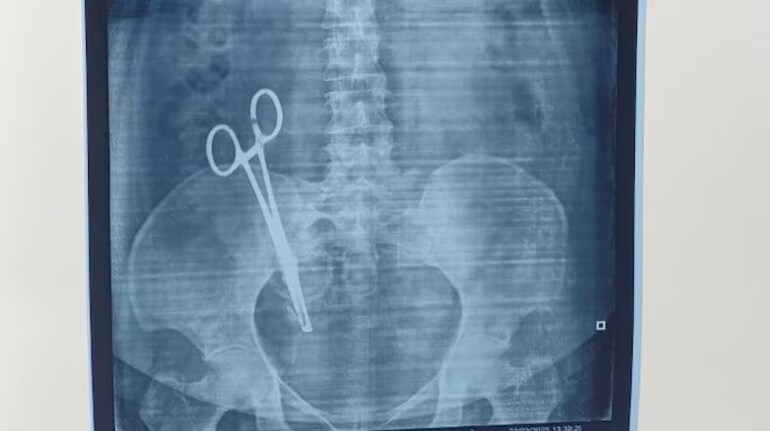

Scissors left in a woman’s stomach after a C-section removed after 17 years

The startling discovery occurred recently when an X-ray at Lucknow Medical College, conducted as part of a routine medical check-up, revealed the scissors lodged in her abdomen.

Image: India Today

A shocking case of alleged medical negligence has come to light in Lucknow, where a woman unknowingly carried a pair of surgical scissors in her stomach for 17 years following a cesarean section. Sandhya Pandey underwent the C-section at 'She Medical Care' nursing home on February 28, 2008, during the delivery of her child.

Despite consulting numerous doctors over the years, Sandhya’s condition showed little improvement. The startling discovery occurred recently when an X-ray at Lucknow Medical College, conducted as part of a routine medical check-up, revealed the scissors lodged in her abdomen.

Following this revelation, she was admitted to King George's Medical University (KGMU) in Lucknow, where a complex surgery on March 26 successfully removed the foreign object.

KGMU spokesperson Sudhir Singh confirmed the details of the incident, stating that while the operation was challenging, it ultimately succeeded, and Sandhya has since been discharged and returned home.